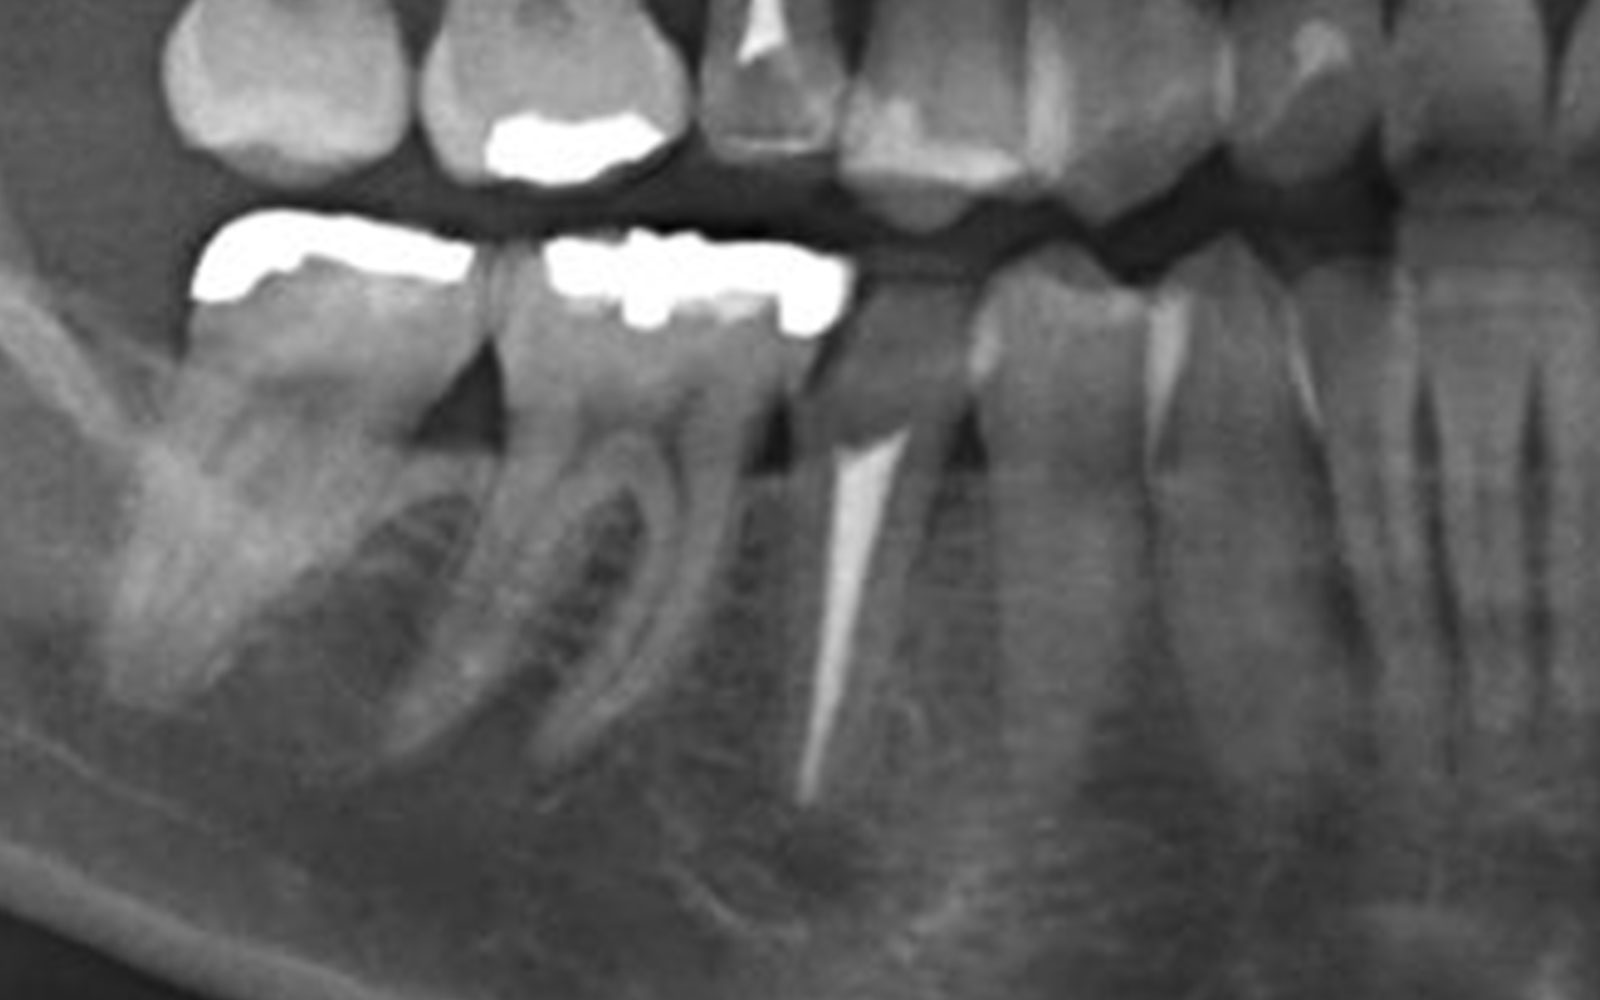

初診時

レントゲン上で左下5番の歯根破折が見られます。ここまで垂直に割れていると抜歯するしかありません。原因は2本の土台で4本のブリッジだったので負担がかかったためだと思われます。